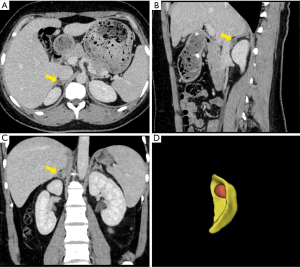

A 27-year-old woman was admitted to our hospital complaining of elevated arterial blood pressure (BP) for more than one year. The highest BP measurement was 180/120 mmHg and her BP fluctuated around 140/100 mmHg after receiving nifedipine and irbesartan. Four months ago, the laboratory examinations in her local hospital revealed serum potassium of 2.88 mmol/L, plasm aldosterone concentration (PAC) of 20.20 ng/dL (reference value, 3.00–35.00 ng/dL), direct renin concentration (DRC) of 31.76 mU/L (reference value, 2.80–39.90 mU/L) and ARR of 0.64. Abdominal contrast-enhanced CT suggested an adenoma on the right adrenal gland (1.25×0.78 cm) (Figure 1). In our hospital, screening test was performed again after hypokalemia correction and anti-hypertension agent changes (terazosin and verapamil sustained-release tablets), but ARR was still negative (Table 1). Confirmatory tests of saline infusion test and captopril challenge test were further carried out considering the high possibility of PA, and aldosterone levels were both not suppressed to the cutoff value. Other laboratory examinations were normal such as routine blood tests, routine urinary tests, liver and kidney function, thyroid function, serum calcium, PTH, midnight serum cortisol, 24-hour urinary free cortisol, and catecholamine metabolites (NMNs). An ultrasonic cardiogram showed the left ventricle was slightly enlarged, and the interventricular septum was thickened, while ultrasonography of the aorta and bilateral renal arteries did not find lesions such as stenosis or dissection.

Given the early-onset hypertension accompanied by spontaneous hypokalemia, a right adrenal nodule, and a normal contralateral adrenal gland and after excluding other known causes of hypertension with hypokalemia, the patient was clinically diagnosed with PA and highly suspected of APA in the right adrenal gland. With the consideration of patient’s demand of being pregnant in the near future, and some studies reported that patients with PA are more likely to develop preeclampsia during pregnancy and have higher risks of cesarean section, premature infants, and low-birth-weight infants (4,5), laparoscopic right adrenalectomy was ultimately performed without undergoing adrenal venous sampling (AVS). Post-surgical pathology and immunohistochemical results of the tumor tissues were consistent with APA (Figure 2A-2C) (anti-CYP11B1 antibody and anti-CYP11B2 antibody were purchased from Merck Millipore, Germany). NGS of the tumor tissues revealed a missense mutation of the KCNJ5 gene: chr11:128781619, c.451 (exon 2) G>A, which was reported as a pathogenic mutation for PA (6) (Figure 2D) (Joy Orient Translational Medicine Research Center Co., Ltd., China).